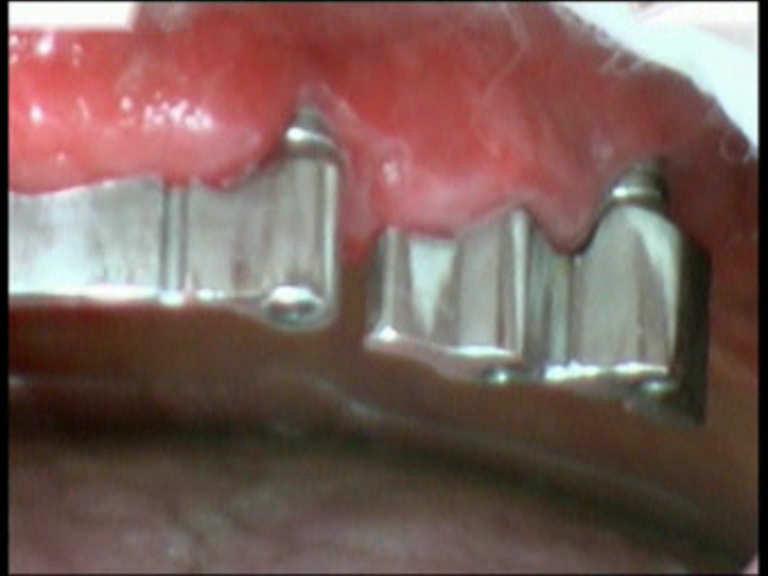

Peri-implantitis

Peri-implantitis is a dental term used to describe the destructive inflammatory process affecting the soft and hard tissues surrounding dental implants. The array of periodontal pathogens found around failing implants (those affected by peri-implantitis) are very similar to those found in association with various forms of periodontal disease.

Diode Laser 810nm

Power: 2.5 Watt,

pulsed 50 Hz

Time On/Off 10ms

Fibre 400 micron